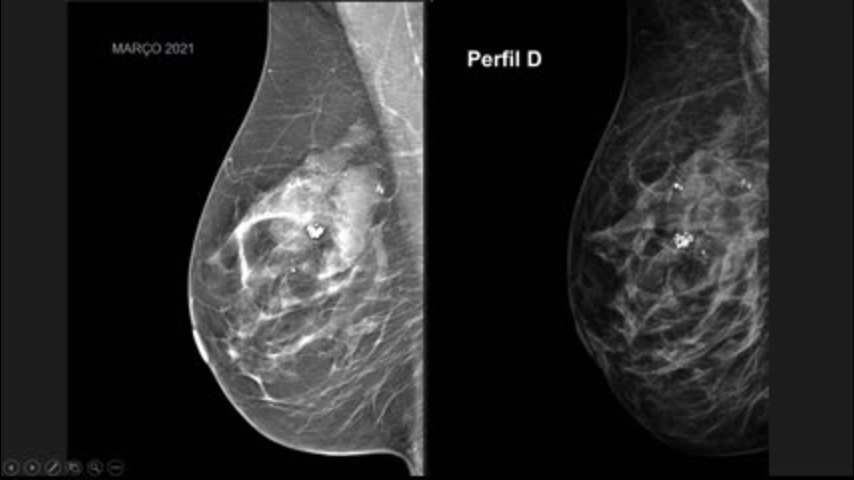

Casos Difíceis e o Que Aprendi com Eles - Caso 1